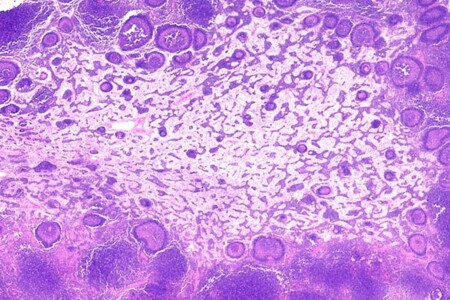

Abscesy neboli hlízy jsou ohraničená zánětlivá ložiska, která se mohou tvořit kdekoliv uvnitř těla nebo na jeho povrchu. Jejich rozměry se různí od drobných puchýřků a vřídků na kůži nebo při vlasových koříncích až po závažnější abscesy zubních lůžek nebo abscesy vnitřních orgánů, například při zánětu slepého střeva (apendixu).